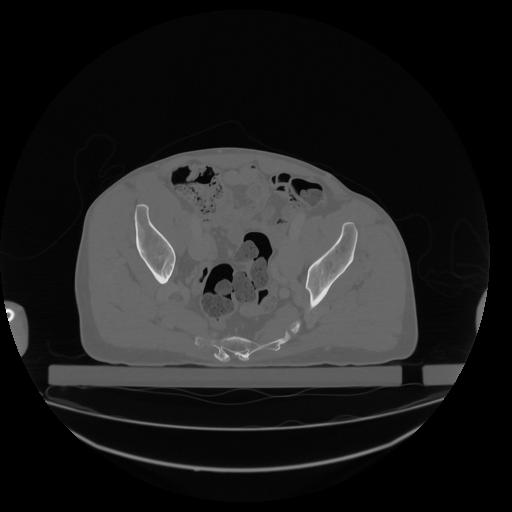

34 CUERPO,CE,Vol,1.0,CUERPO,,